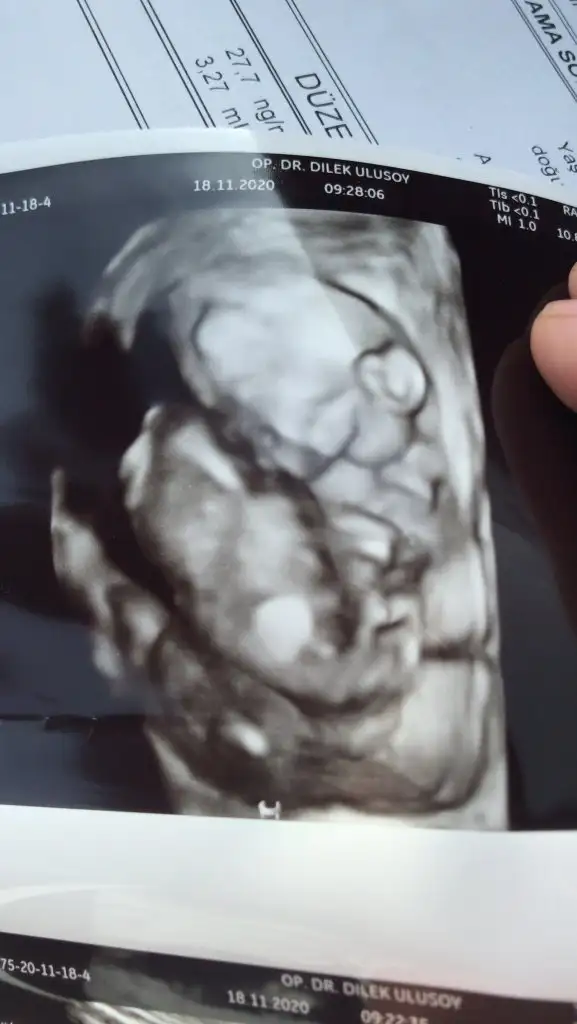

Dün bizim de doktor kontrolümüz vardı. Çok şükür her şey yolunda. 297gr olmuş yavrum. Nisan annelerinde cinsiyeti değişenleri görünce doktora defalarca sordum o da 3 kere kesin kız dedi 2 Aralık’a detaylı randevusu aldım şimdi de onun stresi sardı inşallah hepimiz iyi haberlerle geliriz

Masallah canim bende 18+2de gitmistm dr a yukleyeyim mi fotoyu karsilastiririz kizceleri